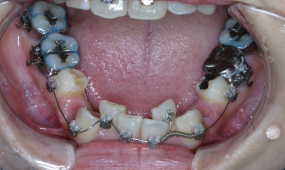

| 口腔内所見 | 歯のサイズが大きく、顎が狭小のため、著しい叢生(乱ぐい歯)の状態でした。奥歯の噛み合わせの問題はなく、側切歯(前歯の2番目の歯)は交叉咬合(上下の歯を噛み合わせた時に、上下の歯列がどこかで交叉している噛み合わせ)の状態でした。 |

| 診断名 | 歯牙サイズの過大、歯槽骨の狭小に伴う叢生症例 |

| 装置名 | マルチブラケット装置、歯科矯正用アンカースクリュー |

| 抜歯部位 | 上下左右4番抜歯 |

歯のサイズと顎骨の不調和が大きいことから、上下左右計4本(小臼歯)の抜歯を提案しましたが、患者さんが非抜歯を希望されたことから、セルフライゲーションブラケット装置(デーモンシステム)で上の歯の排列からスタートしました。しかし歯がキレイに並ぶことにより前歯が出る状態となり、前歯が目立ち自然に口を閉じることも困難となりました。そのため再評価し、患者さんとよく話し合った末、同意を得て上下左右計4本の抜歯に計画を変更しました。

■歯科矯正用アンカースクリューの使用

抜歯後は、上の顎に歯科矯正用アンカースクリューを用いて前歯を後退させました。叢生(歯がガタガタ)は解消され、良好な噛み合わせが確立されました。